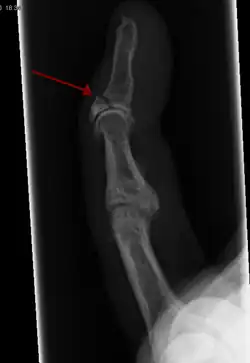

In the fingertip. More images

Avulsion fracture A fragment of bone is separated from the main mass (image shows a Busch fracture)

more images